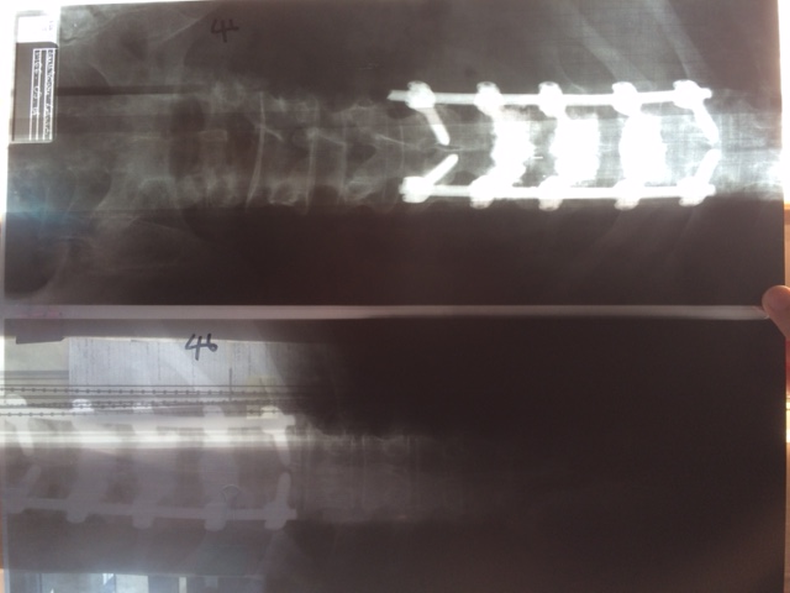

Öt hete volt a mûtét, azóta folyamatosan járok vízi edzésekre, és egyre jobban érzem magam, kivéve azt a huszonöt centis vágást, ami a hátamon van, mert az még húzódik. Ja, és kicsit furcsa érzés, amikor hanyatt fekszem, olyan, mintha folyamatosan feküdnék valamin, csakhogy az a valami a testemen belül van – mondta Bunkoczi, aki azt is elárulta, a második mûtétre azért volt szükség, mert folyamatosan fájt a dereka, és így stabilizálták tovább a már megmûtött gerincét.

– Összesen tizenkilenc órán keresztül mûtötték a gerincemet, úgyhogy most már csak jó lesz! Én úgy készülök, hogy jó lesz, és akkor januárban újra autóba ülhetek. Öt hónapom van addig, ami ha akarom sok, ha akarom kevés, de minden nap teszek valamit azért, hogy vissza tudjak térni a versenyzéshez, mert ez mindennél jobban motivál.”